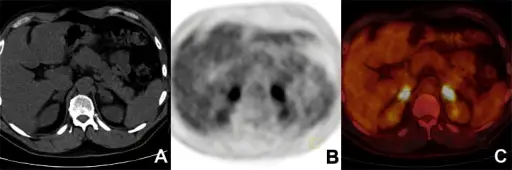

Common sites for systemic dissemination of tuberculosis (TB) include:

- Kidneys (sterile pyuria)